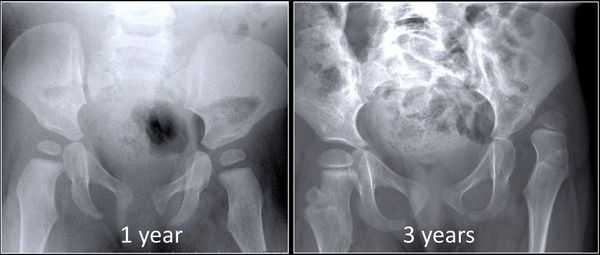

Инструментальные исследования: на рентгенограммах тазобедренных суставов при подвывихах отмечается смещение головки бедра латерально, часть головки остается непокрытой крышей, линия Шентона нарушена, головка деформирована, скошенность крыши вертлужной впадины.

При вывихах головка бедра смещена вверх до крыла подвздошной кости, находится во вновь образованной впадине, расположенной проксимально от первоначальной впадины.